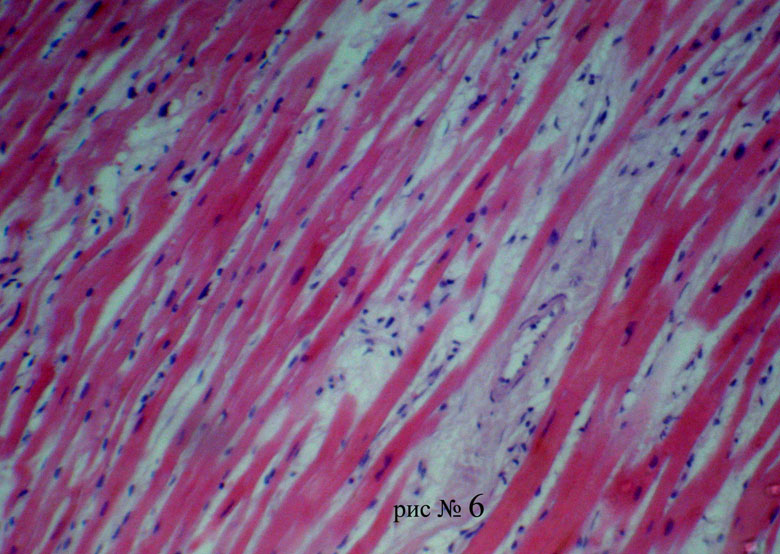

Межуточный миокардит: гистологические исследования